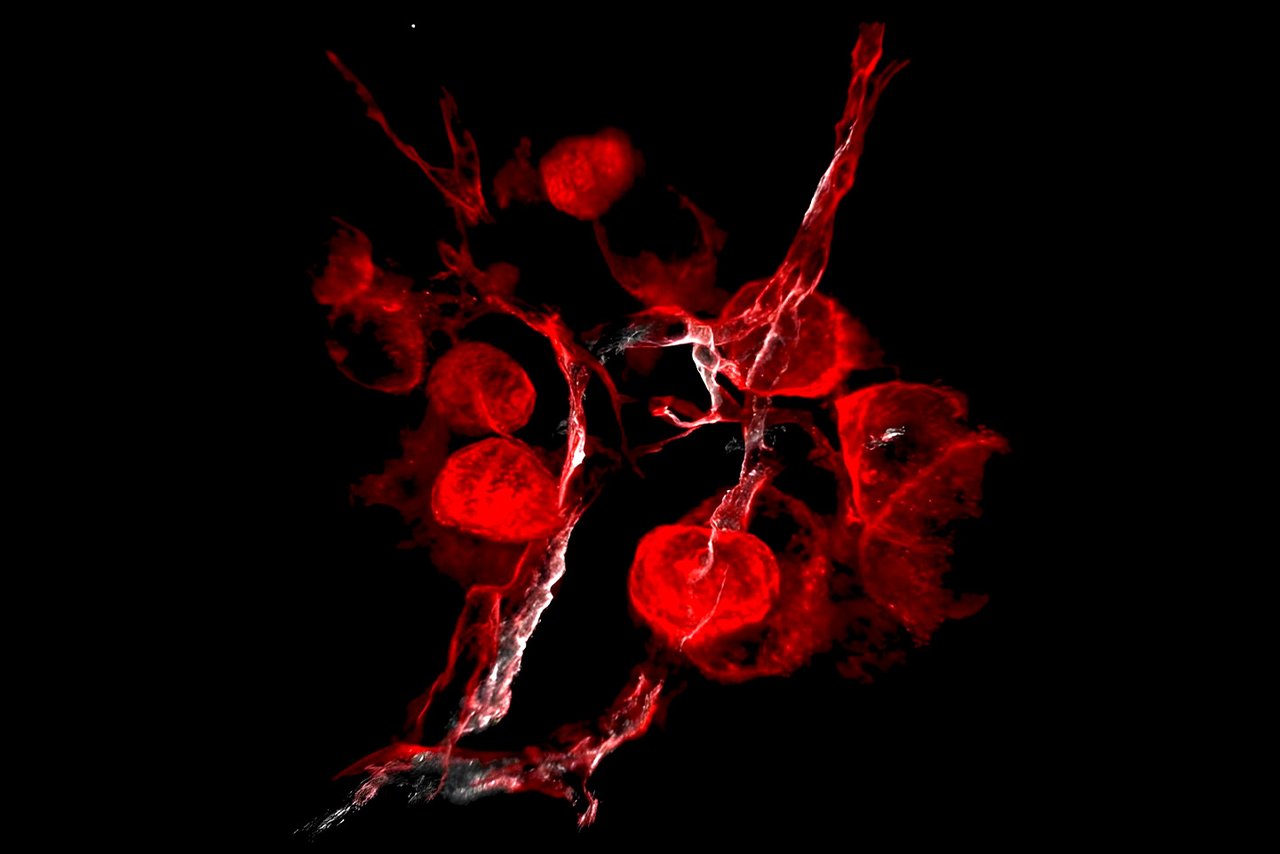

NIHR GOSH BRC Partners’ favourite: Nasal COVID-19 factories

Entered by Dr Maximillian Woodall, UCL GOS ICH Research Fellow, Dr Samuel Ellis, UCL GOS ICH Research Fellow and Dr Andreia Pinto, Leica Microsystems, this striking collection of shapes and colours shows human nose cells infected with SARS-CoV-2 (viral particles in red). It was taken as part of a study investigating how SARS-CoV-2 (Covid) infection differs with age.

From the image, it is possible to see that some cells, such as epithelial cells (dark green) are much more susceptible to infection than others like mucus secreting cells (yellow).